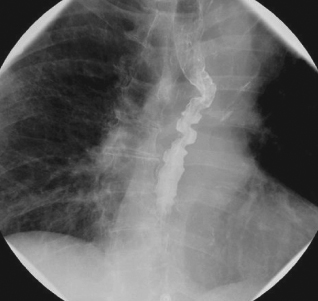

Mrugesh Patel, MD; Mario J. Madruga, MD

<p>An 80-year-old woman presented with difficulty in swallowing, which had gradually worsened over 4 weeks. She complained that food was getting stuck and that she frequently had to sit upright to be...